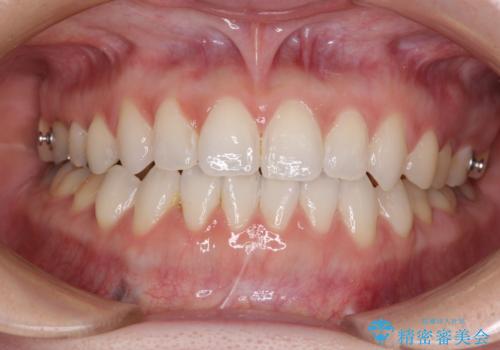

前歯のデコボコをすっきりと インビザライン矯正

- 前歯のデコボコを治したいとのことで来院された患者様です。

下顎が前方位にある方であったため、下顎の歯列全体の後方移動とIPR(歯と歯の間を削る)によってデコボコが解消するように設計し、インビザラインにより治療を行うこととしました。